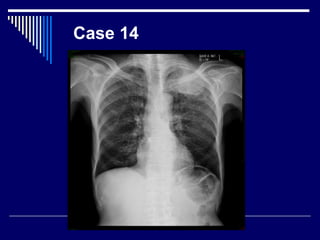

Case 14

Findings

• CXR

• Lung apical lung mass (1)

• Destruction of left 4th rib (2)

• CP angles = clear (1)

• Right lung = normal (1)

• Dx : pancoast tumor (4)

• What Next = CT chest (1)

Findings • CXR • Lungapical lung mass (1) • Destruction of left 4th rib (2) • CP angles = clear (1) • Right lung = normal (1) • Dx : pancoast tumor (4) • What Next = CT chest (1)